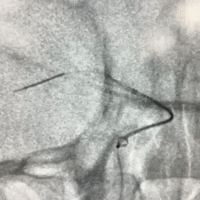

输送Nuva®血流导向密网支架 TJED-D-5.5-20顺利到位,释放头端及定位支架远端。

继续释放Nuva®血流导向密网支架。